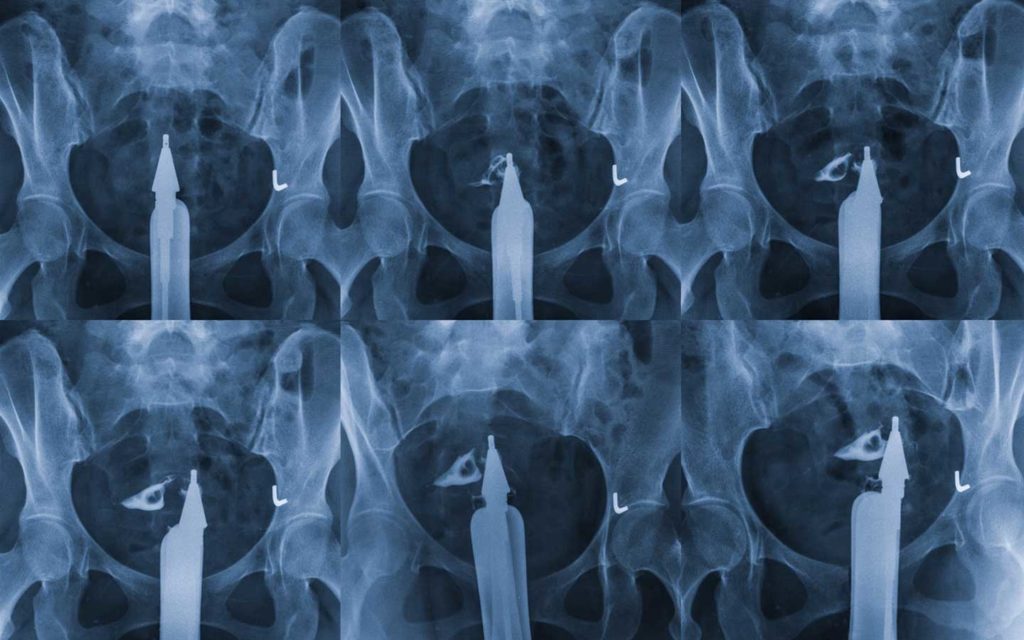

From www.gettyimages.in

Fallopian Tubes Obstruction Photos and Premium High Res Pictures Dye X Ray Fallopian Tubes Hysterosalpingography (hsg), also known as uterosalpingography, [ 1 ] is a radiologic procedure to investigate the shape of the uterine cavity. Once the area is numbed, your ob/gyn will use a small, thin tube or catheter to insert liquid dye into your cervix, which is used to see the outline of your uterus and fallopian. It often is used to. Dye X Ray Fallopian Tubes.